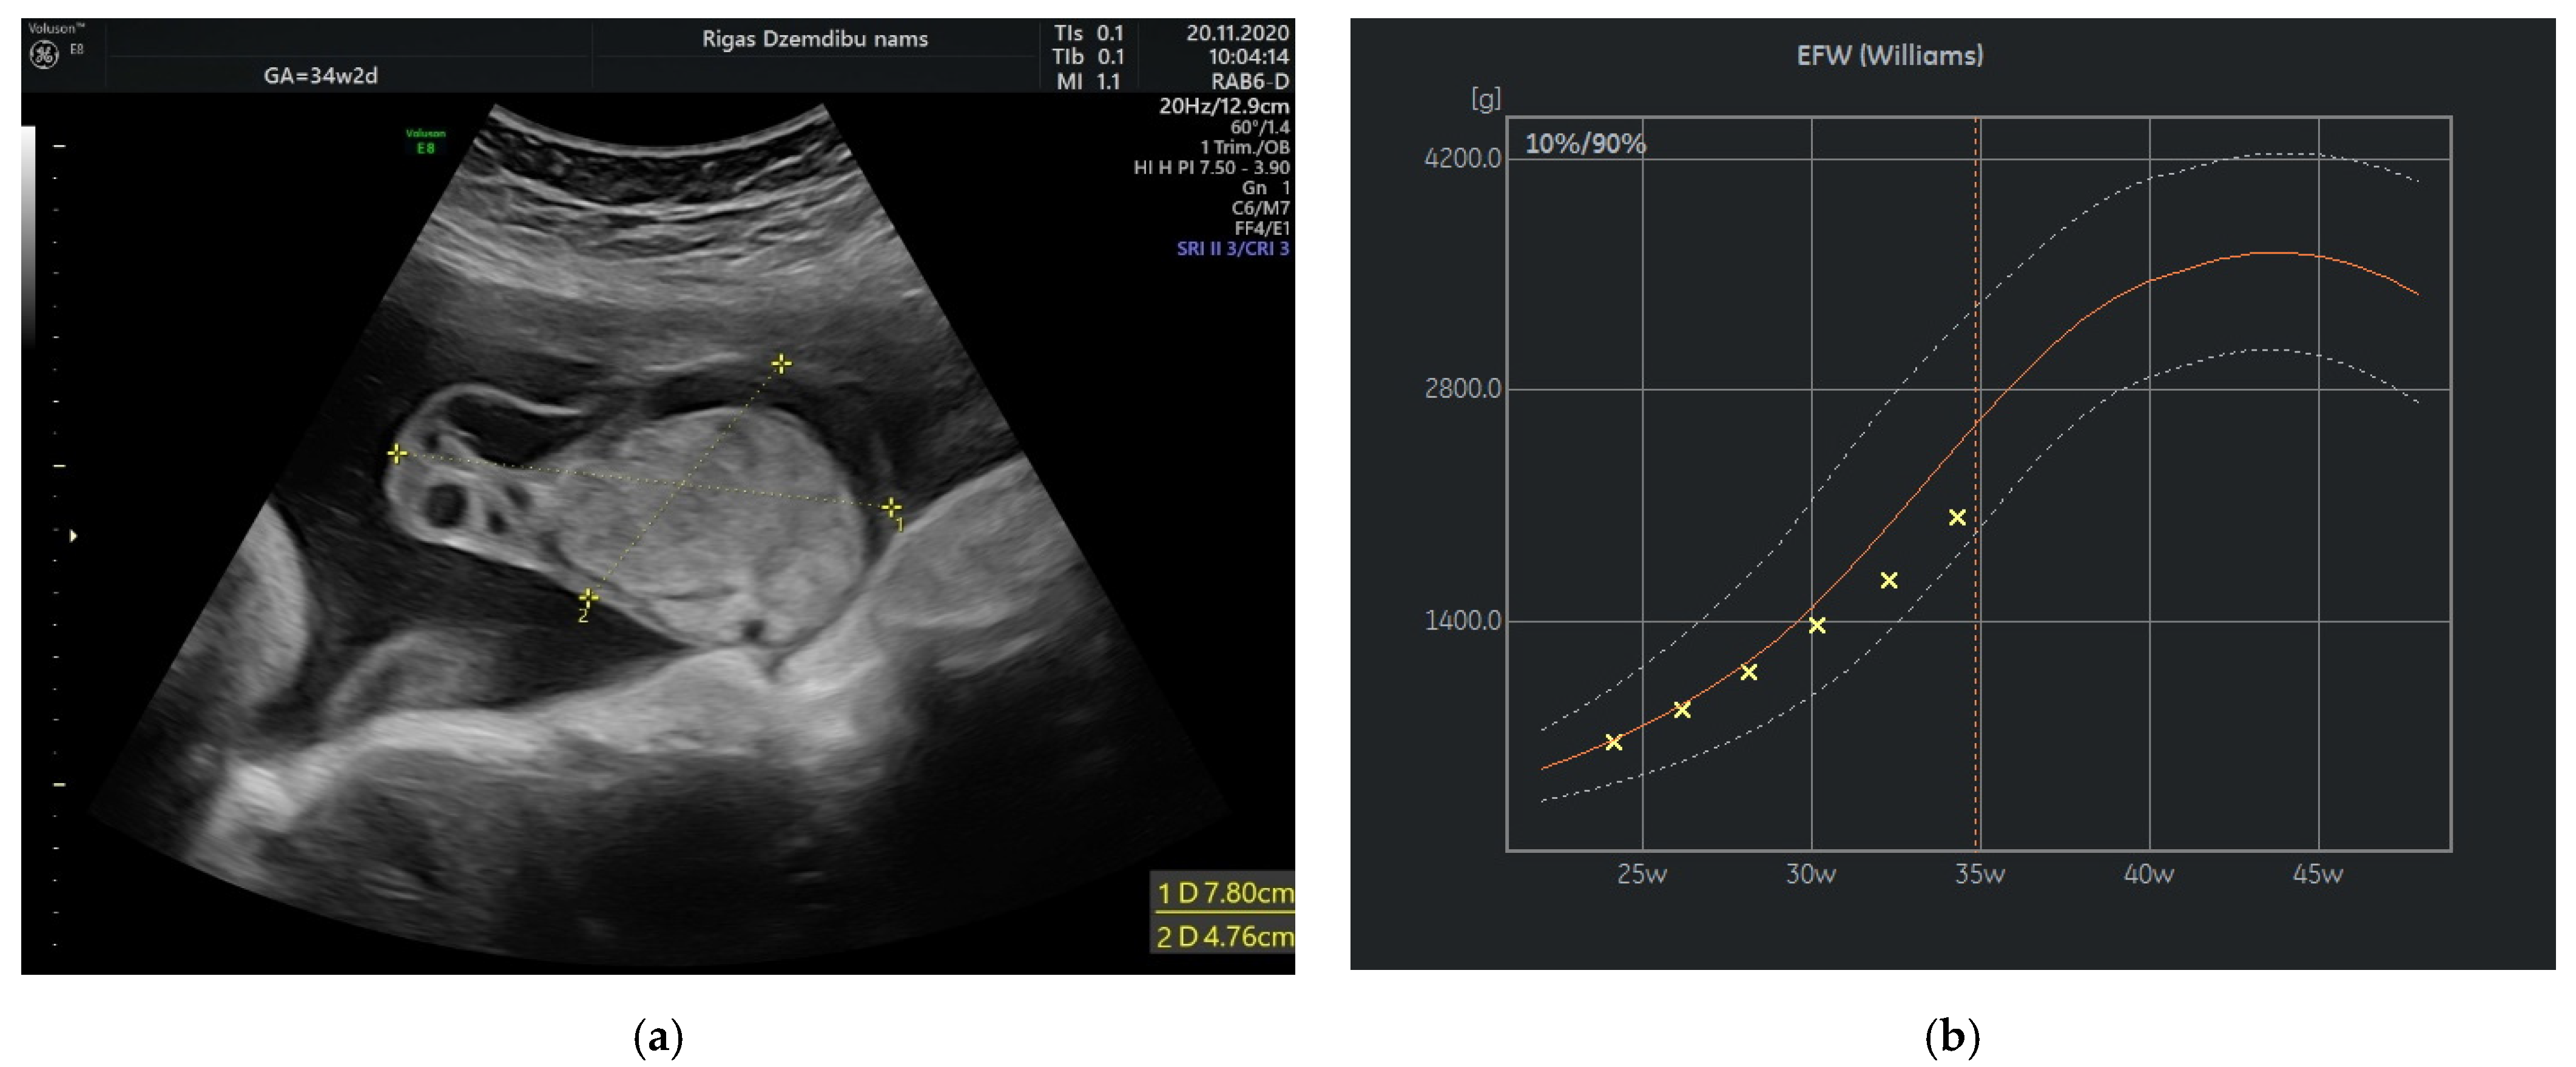

The size of the solid component was 3.4 × 2.3 cm and did not change during the pregnancy. The umbilical arteries and vein were running around and through, extra vessels were not observed in the tumor (Figure 2a). At the follow-up, the mass had rapidly enlarged in the size, from 285.32 cm3 at 26 weeks to 1929.36 cm3 at 32 weeks (Figure 2b). As well the reduction of fetal growth was observed from 30th week of gestation (Figure 3b).

Figure 3.

(a) Tumor appearance at 34 + 2 weeks; (b) Growth chart, estimated fetal weight by weeks.

At 34 weeks of gestation reduction in the size of tumor’s cystic component with freely floating superficial membranes was observed (Figure 3a). That resembles the process of rupture of the membranes without any signs of bleeding. Normal ACM PSV (49.4 cm/s) was recorded during examination of the fetus. At that time the umbilical mass decreased in size enormously and measured 120.45 cm3.

In our case the angiomyxoma was progressively growing from 24 weeks until 32 weeks. That have leaded to slowly decrease in estimated fetal weight from 50% at 24 weeks to 10% at 37 week of gestation and reduced abdominal circumference (AC) from 45% at 24 weeks to 1.1% at 34 weeks and then slightly increase in AC to 4.1% at 37 weeks. The explanation of this can be rupture and decrease in size of the angiomyxoma that have promoted better flow in umbilical vessels.